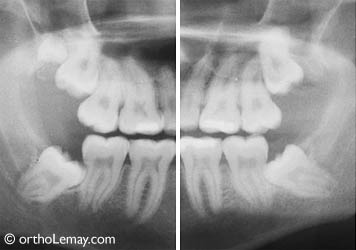

Dents de sagesse supérieures et inférieures incluses et qui s’appuient contre les deuxièmes molaires chez un homme de 21 ans. Il y a même 2 dents de sagesse supérieures sur la radiographie de droite! Ces molaires ne sortiront pas et peuvent endommager d’autres dents.